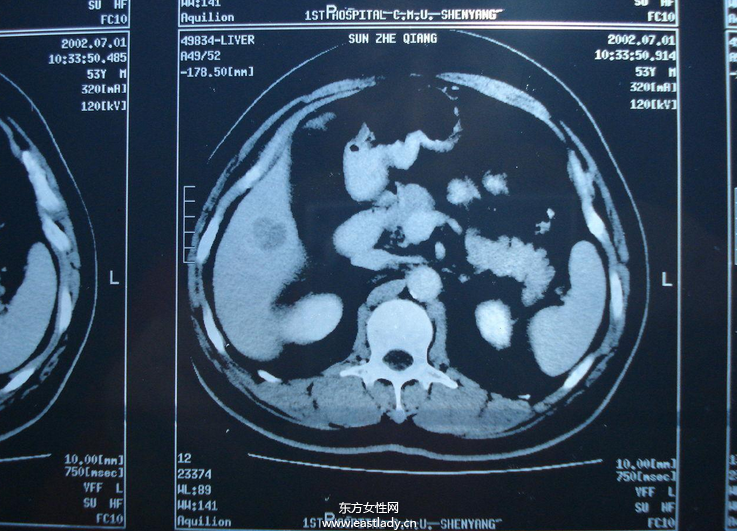

所谓肝癌介入治疗,是指经过股动脉插管将抗癌药物或栓塞剂注入肝动脉的一种区域性局部化疗,它是目前非开腹手术治疗肝癌的首选治疗方法,疗效已得到肯定,是中晚期肝癌治疗最佳手段。

其主要原理是采用局部靶向药物灌注、肿瘤血管栓塞及氩氦冷冻消融等方式集中杀灭肿瘤细胞,最大限度地降低肿瘤负荷,可逆转部分患者肝癌分期,使不能切除的肝癌病例转化为可切除的肝癌病例。

并且其优点明显,首先是其治疗时操作简单易行,安全可靠,不像大型手术需要全身麻醉及大的手术切口,如此年龄偏大及身体较弱的患者也可以承受;其次其疗效确切,治疗后可短期内使甲胎蛋白迅速下降、肿块缩小、疼痛减轻,且对于部分肝癌可缩小体积后作二部切除。